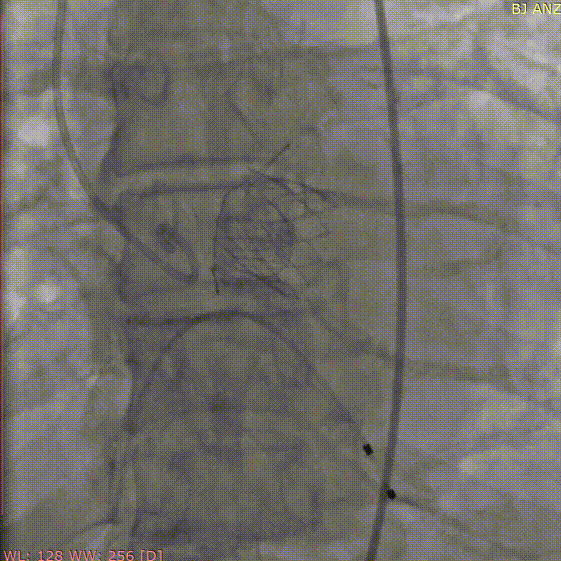

术前造影

定位件入窦

释放瓣膜

术后造影